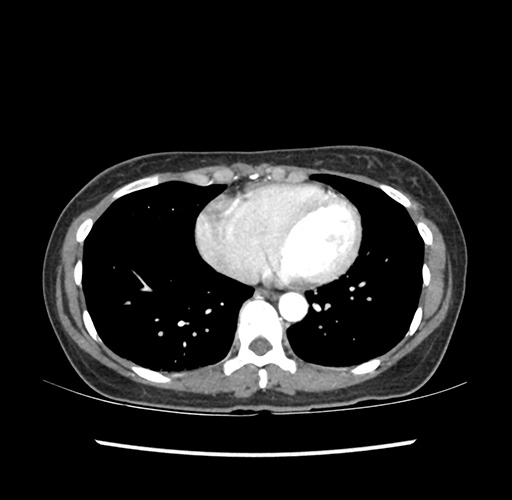

Imaging Analysis

Look through the patient's CT scan to identify any areas of concern for the necessary procedure.

Based on your CT findings, which issue(s) would give reason for "planned slowing down moment(s)" in this case?